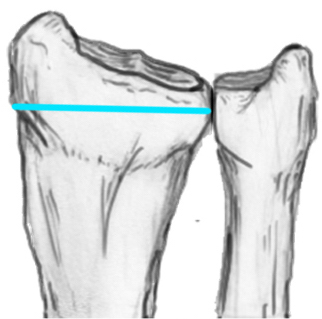

Radial angles

| Volar tilt mean 11° | Radial inclination mean 22° | Radius mean 11 mm longer than ulna |